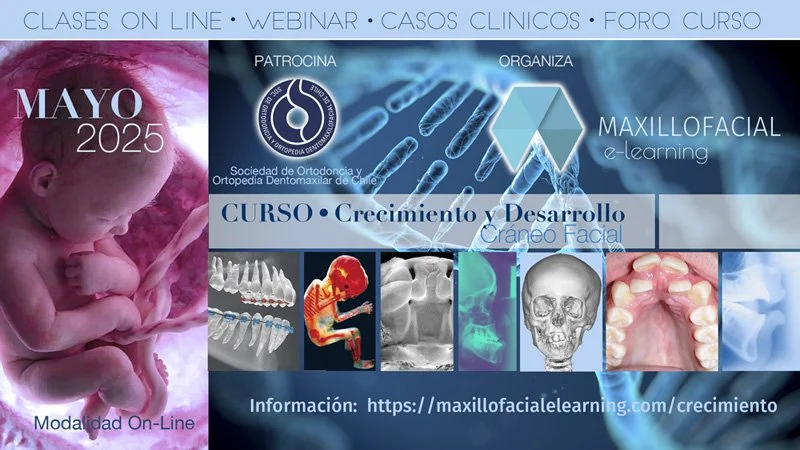

Nuevo canal gratuito en YouTube: Crecimiento y Desarrollo Cráneo-Facial.

Te invitamos a conocer este nuevo canal y a suscribirte (en la próxima sección) para recibir actualizaciones de los nuevos contenidos y poder acceder a los seminarios abiertos sobre diferentes temas y, con profesionales de diferentes áreas.

Los métodos E-Learning cuentan con clases on-line, foro, correo electrónico y webinar para una comunicación en tiempo real con nuestros alumnos.

Dr. Juan Argandona P.

Director de curso

Crecimiento y Desarrollo Cráneo Facial